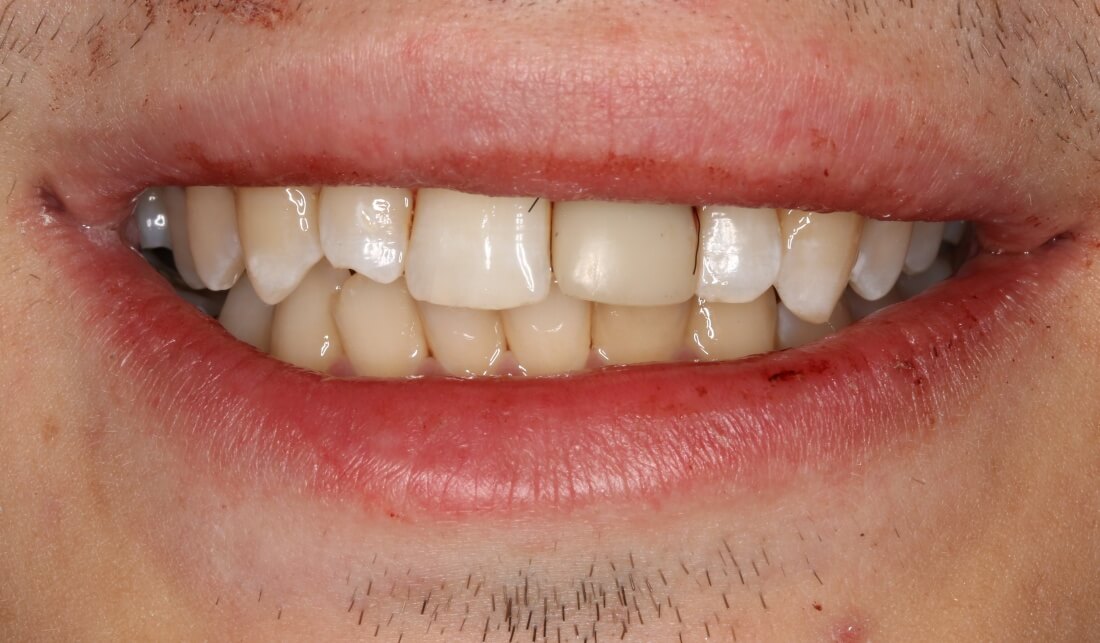

Около трёх лет назад к нам в клинику обратилась пациентка Мария, на момент обращения ей было 45 лет. Её беспокоила ситуация с передними резцами:

В ходе беседы она рассказала, что лечит эти зубы всю сознательную жизнь — их депульпировали («удалили нерв») из-за последствий травмы еще в школьном возрасте, и после этого каждые несколько лет (а то и чаще) ей приходилось перелечивать каналы, менять коронки, вкладки и т. д.

В результате, зубы приобрели очень уж нездоровый вид (см. фото выше). Вдобавок, всё усугубилось существенным снижением качества жизни — коронки и вкладки из зубов постоянно выпадают, десна вокруг них кровоточит при чистке…. Кроме того, Марию не покидает ощущение того, что эти зубы могут просто вывалиться в самый неподходящий момент. Именно это заставило её обратиться в нашу клинику.